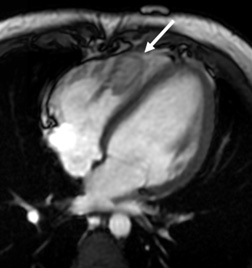

Cancer-related Heart Disease

Description: There are many types of cancers that can affect the heart, causing tumors or blood clots in the heart muscle and heart chambers. Cancer treatment (chemotherapy and radiation) can also affect heart function.

Why MRI: Heart MRI can be used to figure out the type of mass or tumor inside the heart to help your doctor decide what treatment or other testing may be needed. Heart MRI can also check the function of the heart during cancer treatment.

Images: Heart function, mass